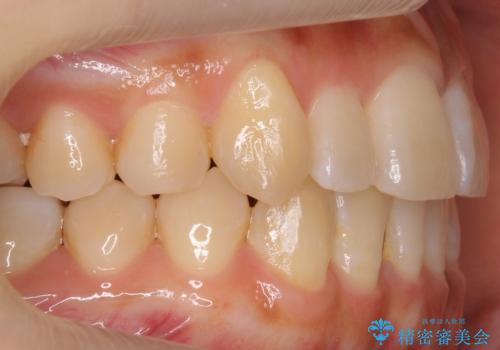

八重歯 インビザラインで抜歯矯正 ただし1本のみの抜歯で済みます

- 八重歯を治したいと来院。

古典的な治し方ですと上下左右4本抜歯してワイヤー矯正です。

今回は口元も出ていないうえに、右上のみの八重歯のため奥歯を後ろに下げて治療しました。

ただし、下の前歯は入りきらない為1本のみ抜歯しています。

右上の犬歯をおろしてくるのに、顎間ゴムを使用しています。